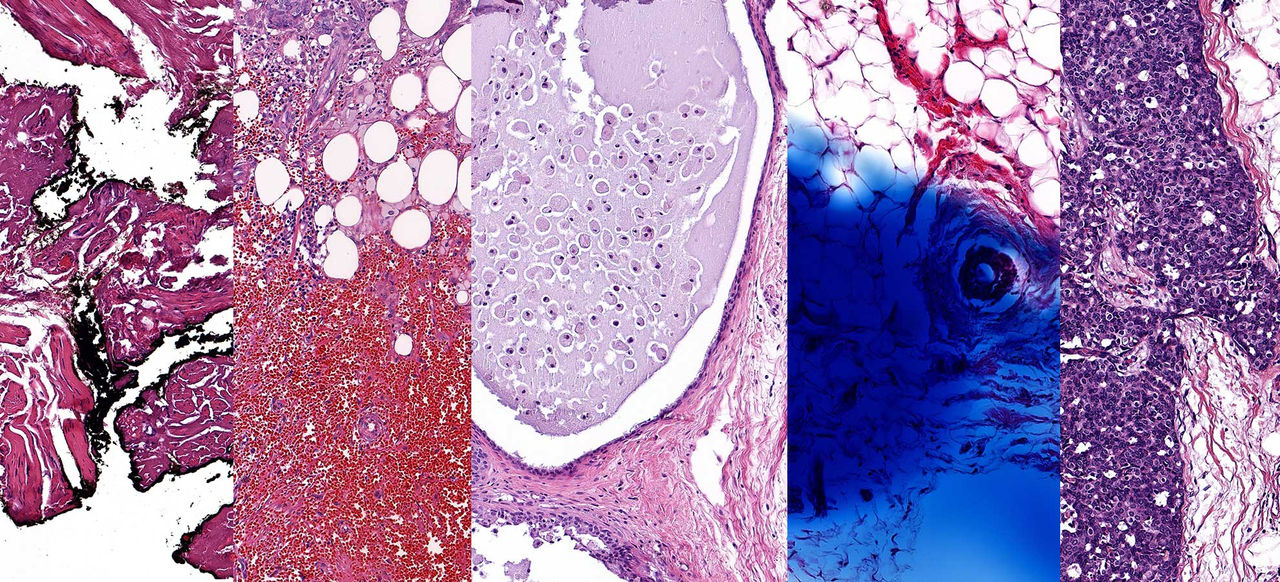

Every two years, ACS sent participants a follow-up questionnaire, and if someone reported that they had breast cancer, their hospital would send tumor samples to ACS. The samples were made by soaking the removed tumor in a solution that stops cellular activity, putting it in a block of wax, taking a very thin slice out of the block, staining the slice to show the different parts of the cells, and then putting the slice in a glass slide.

Since the study began, ACS has collected over 1,700 slides from women diagnosed with breast cancer. These slides can provide critical clues to help prevent and treat breast cancer—but identifying those clues was a challenge.

The next step was to scrub the tissue slides of any inconsistencies that could skew the analysis. A lot has changed since 1992 in terms of how pathologists treat the slides. In the 90s, pathologists mixed the tissue dye by hand, which means there’s been a lot of color variations in the slides over the years. “We had some slides that were a light pink and some that were a dark purple,” says Gaudet. Also, some pathologists would write directly on the slides with Sharpies, circling a tumor or making notes.

Once we flagged and filtered out any irrelevant markings or coloring, we were able to set up unsupervised machine learning. We told the machine to identify patterns in the tiles and create 10 clusters. Clustering is when the machine groups similar patterns, like your phone automatically searching through your photos and creating a photo album of your daughter.

The machine created some clusters that the team understood, like identifying the grade of cancer, which validated that the machines were on track. “But there are also new patterns that we’re not yet unable to understand why they were clustered, which was the goal,” says Gaudet. “For example, clusters two and three—well, to my eye they look exactly the same but that’s the whole premise of the project, for the machine to identify differences that the human eye can’t.”